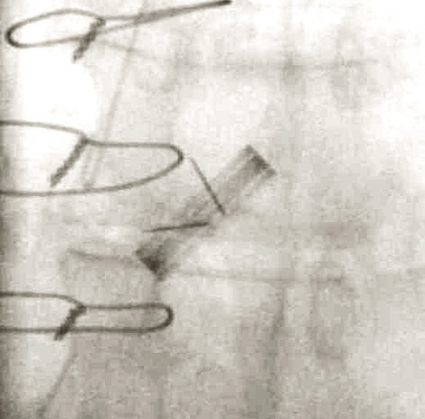

Klaffilmning med röntgengenomlysning visualiserar klaffskivornas rörlighet, och eventuell obstruktion med nedsatt rörlighet hos en eller bägge klaffskivorna kan enkelt identifieras. Metoden kan dock inte diskriminera mellan pannusbildning och trombos, inte heller kan graden av obstruktion bedömas [6].